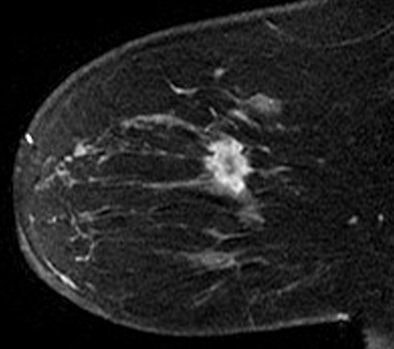

| Contrast-enhanced fat-suppressed T1-weighted sagittal MR image of right breast shows mildly enhancing mass (arrows) that corresponds to asymmetry. |